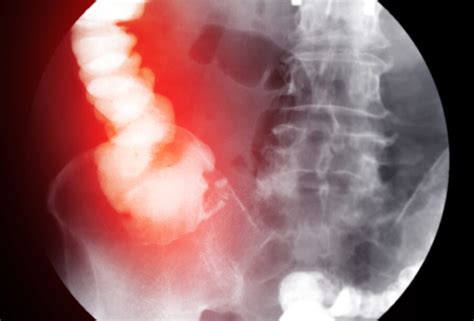

- Vaizdiniai tyrimai: Pilvo ultragarsas ir rentgeno tyrimai gali padėti nustatyti obstrukcijos vietą ir pobūdį.

Įtariant plonosios žarnos užsisukimą, turėtų būti nedelsiant atliktas kompiuterinės tomografijos tyrimas. Apžvalginė pilvo srities rentgenograma gali būti naudinga diagnozuojant riestinės žarnos užsisukimą, kurioje gali būti matoma išsipūtusi, apverstos U raidės pavidalo žarnos kilpa.